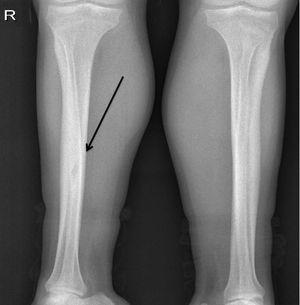

Presentamos el caso de un varón de 38 años con insuficiencia renal crónica terminal secundaria a nefropatía por reflujo, en programa de hemodiálisis desde los 23 años. Presentaba hiperparatiroidismo secundario tratado con paricalcitol por intolerancia digestiva a cinacalcet, con hormona paratiroidea (PTH) en torno a 1900 pg/ml. Consultó por una tumoración indolora, dura y sin signos inflamatorios, de un mes de evolución en el hombro izquierdo (figura 1). La serie ósea (figura 2 y figura 3) y la tomografía axial computarizada cérvico-torácica (figura 4) mostraron una imagen ovoidea, hipodensa y de borde no escleroso en la diáfisis de la tibia derecha y lesiones osteolíticas expansivas, con importante adelgazamiento de la cortical en las zonas distales de ambas clavículas, la mayor (4 cm de diámetro) en el lado izquierdo, que corresponden a tumores pardos debidos al hiperparatiroidismo secundario. Se realizó una paratiroidectomía total, observándose adenomas en las glándulas izquierdas y descenso inmediato de la PTH hasta 0,3 pg/ml.

Figura 1. Masa dura, indolora y sin signos inflamatorios en el hombro izquierdo